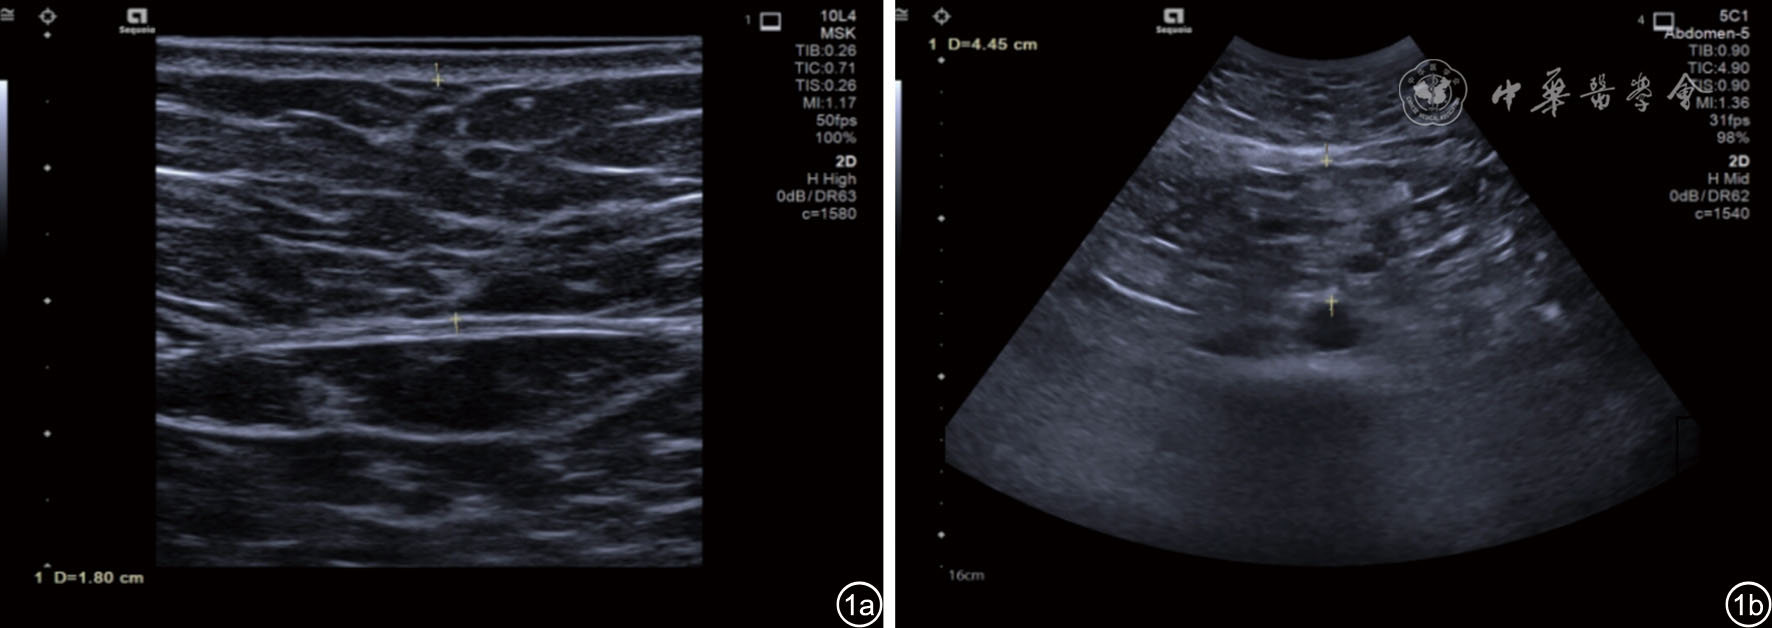

图1 高甘油三酯血症患者皮下脂肪厚度、内脏脂肪厚度测量超声图像。图a为皮下脂肪厚度测量,使用线阵探头9L4于腹部正中脐上l cm处测量皮肤层后缘至腹直肌内侧前缘的距离,测值为1.80 cm;图b为内脏脂肪厚度测量,使用凸阵探头C5-2在同一部位测量腹直肌内侧后缘至腹主动脉前壁的距离,测值为4.45 cm